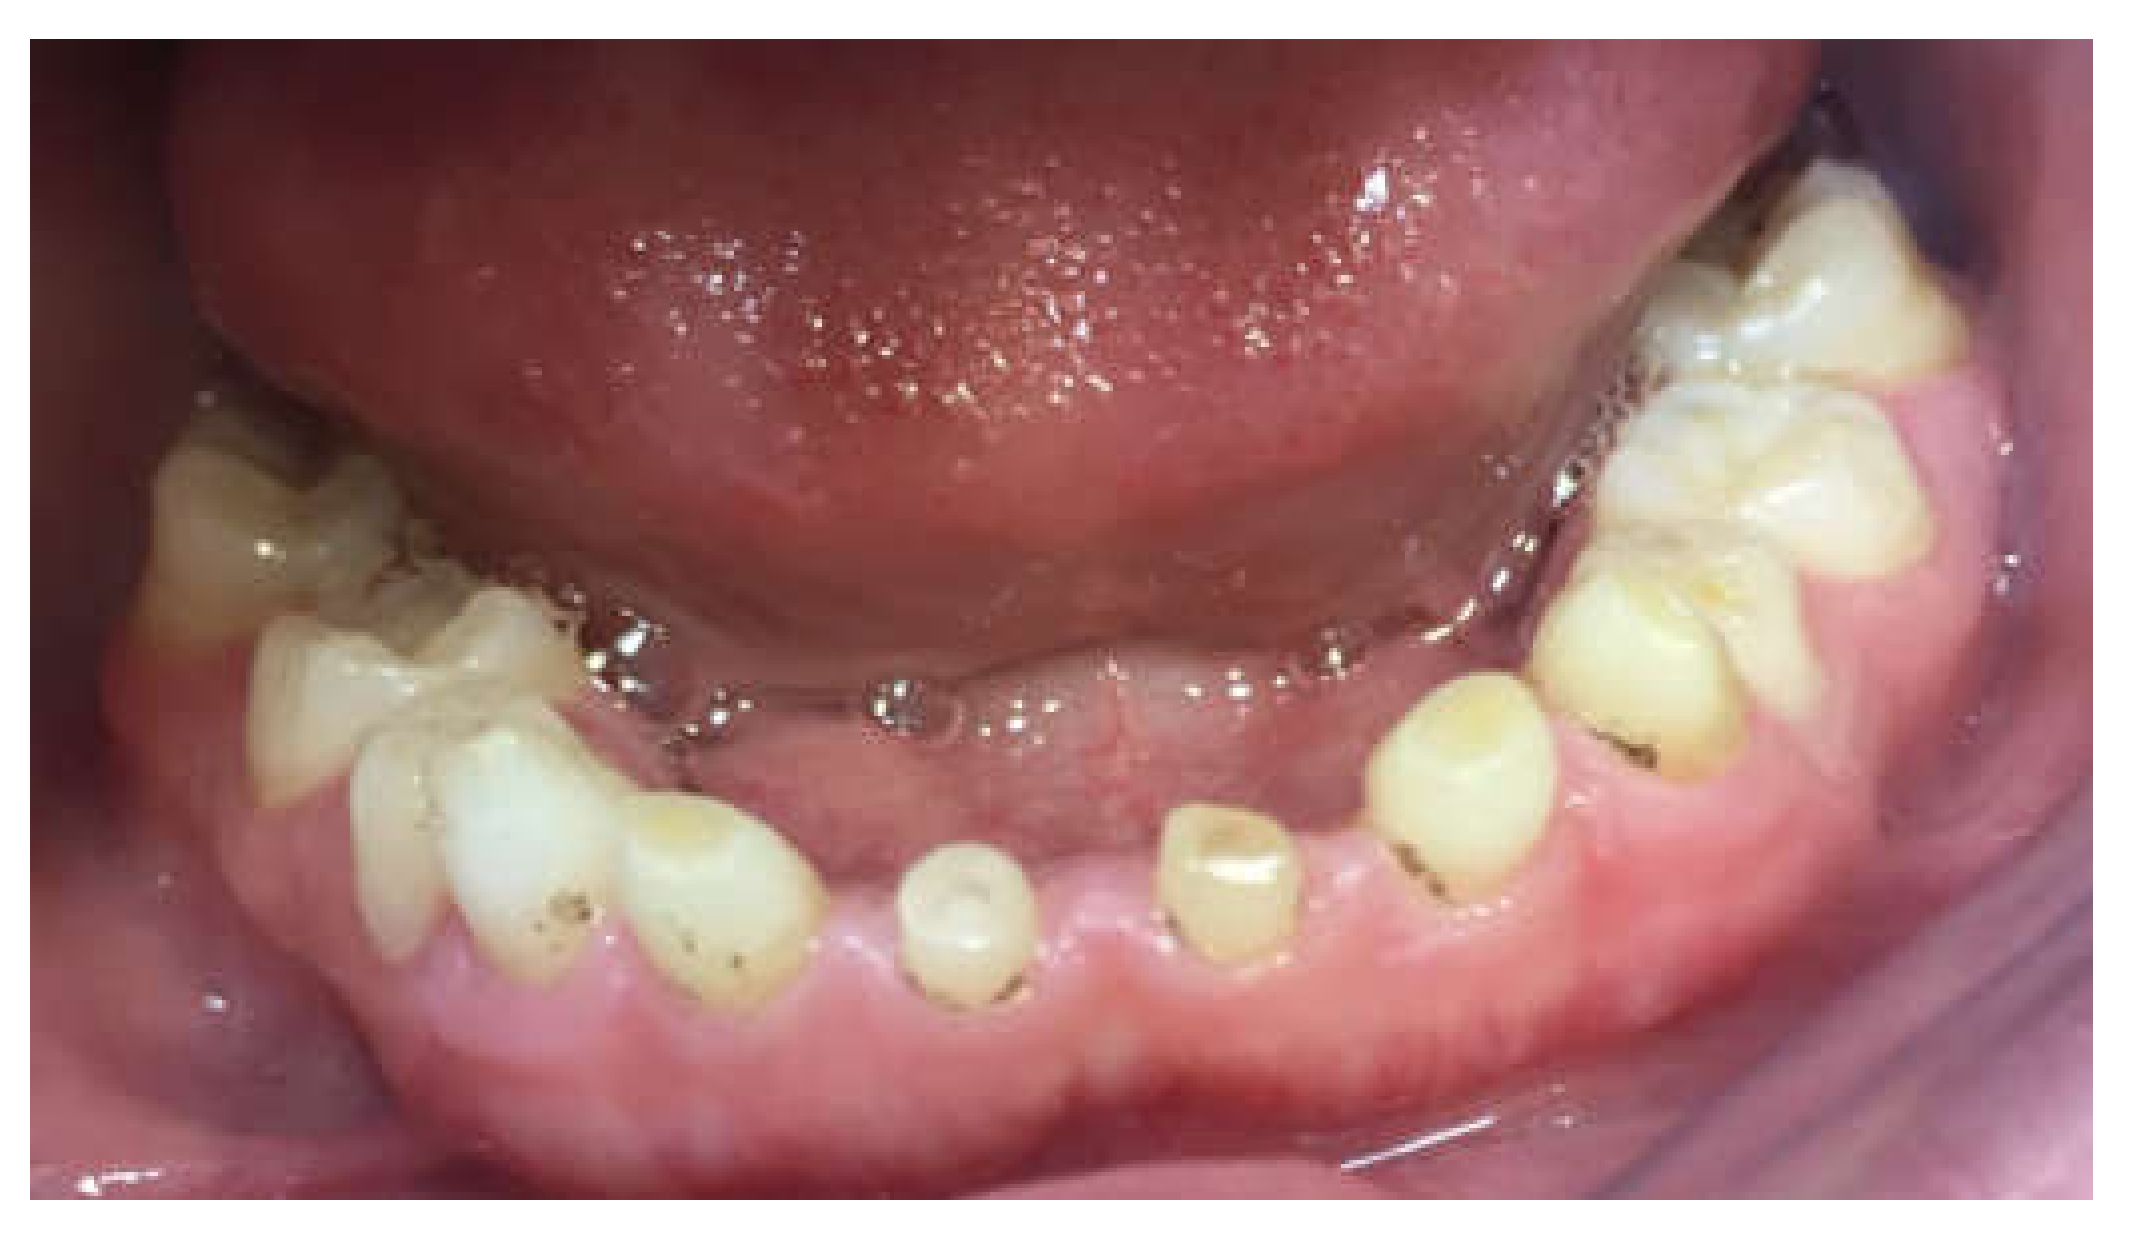

Primary Teeth Supported Fixed Prosthesis—A Predictable Treatment Alternative

2. Materials and Methods

3. Results